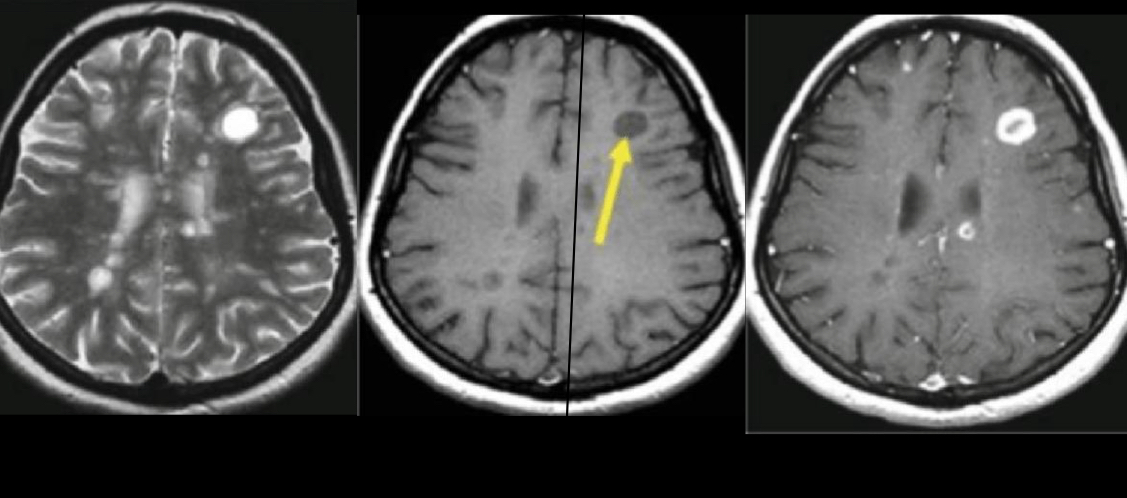

q ves en imagen

A

hiperintensidades calloseptales en T2 Y FLAIR

Peque, lineales, ovoide

Periventriculares

Dedos dawson

en t1 q verías

hipointenso-> BLACK HOLES: crónica

Para q se usa t1 mas galodinio

ver captación: aguda: activa